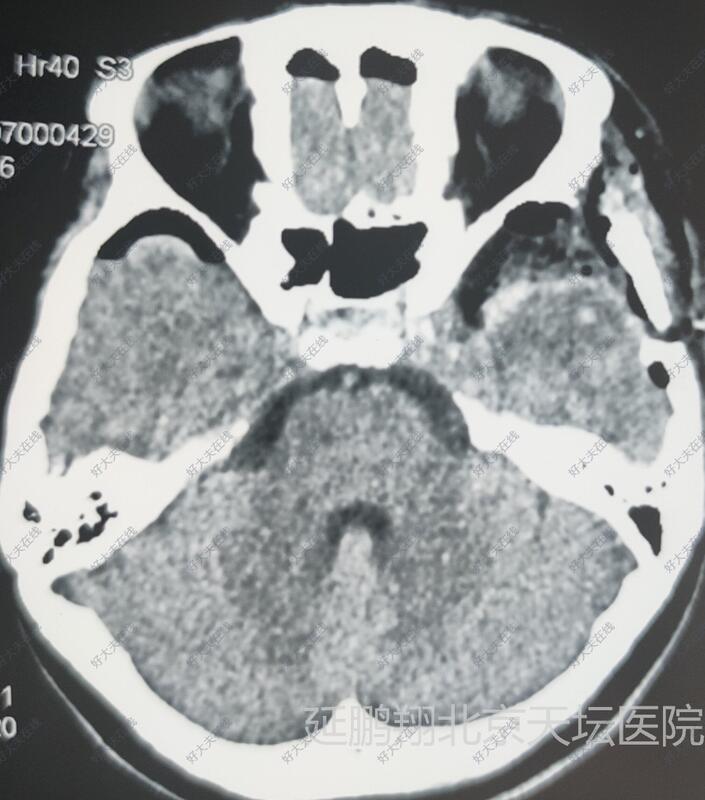

女性,48岁。发作性心悸,心烦,头晕11月。CT和MRI显示左侧鞍旁脑膜瘤,与海棉窦及颈内动脉及大脑中动脉关系密切。

术后病人全麻苏醒顺利,生命体征平稳,四肢活动好。常规术后六小时复查头颅CT显示肿瘤消失。